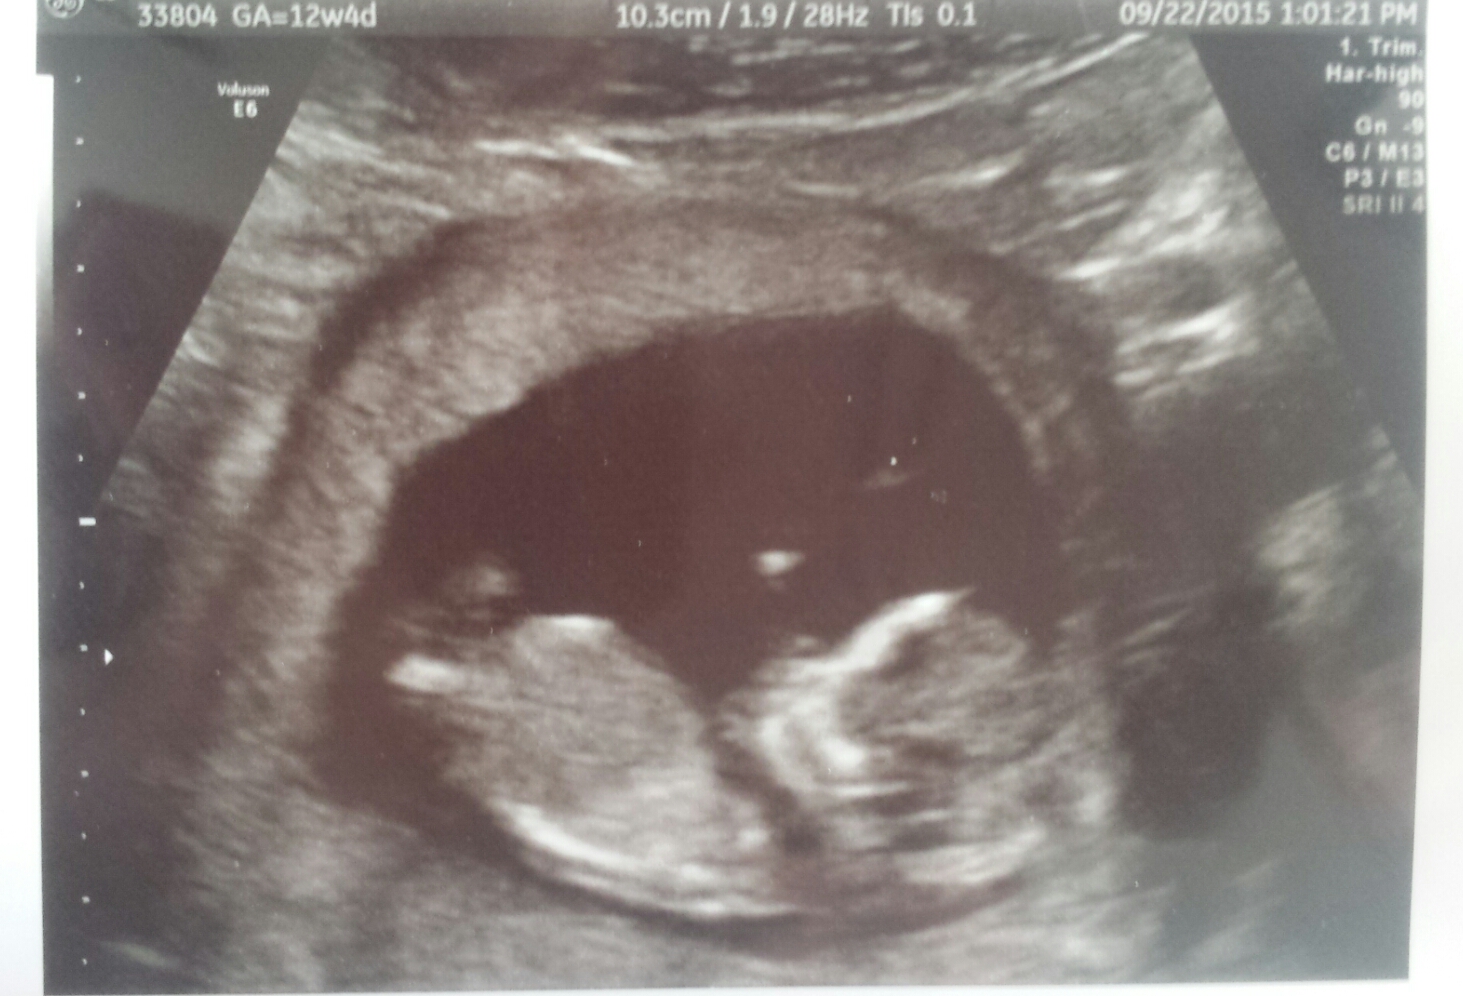

Here is my sweet little boy (we got our all clear Panorama results back today) at 12 weeks 4 days (yep, the due date moved up)! Heartbeat was 167 and he was a happy, wiggly worm. I've been bumped into March, so I wanted to wish you all the best.